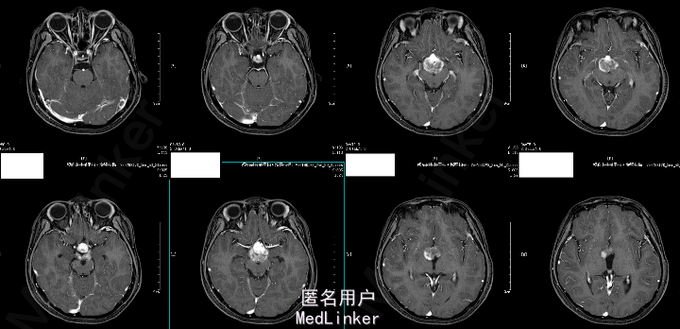

诊断:鞍上区恶性肿瘤:颅内生殖细胞肿瘤 处理:放疗。(3D-CRT 36GY/FX),胸腺肽增强免疫力及副作用对症处理。 (2015-06-24复查头颅MR结果如下)